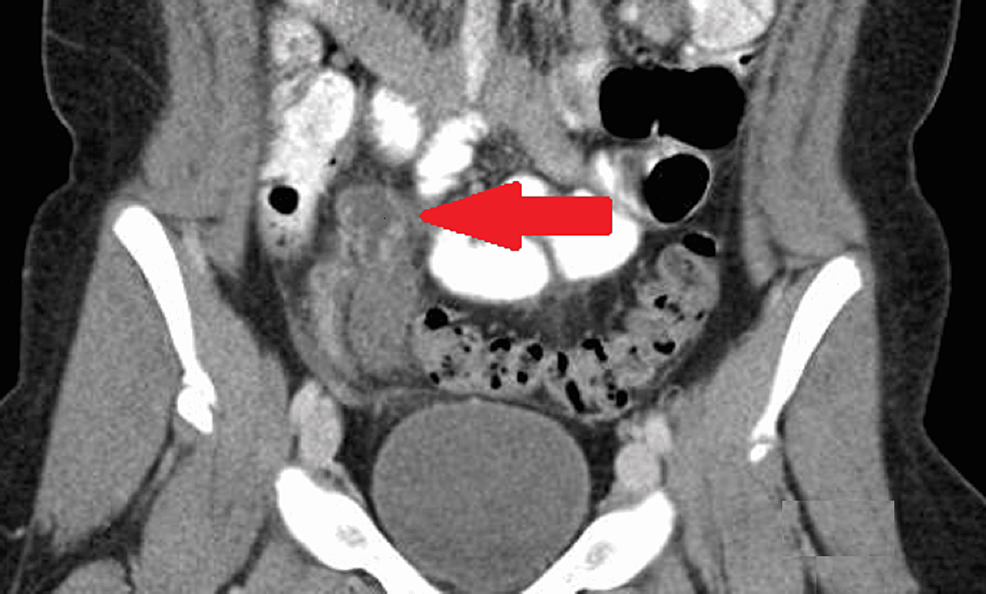

(PDF) The Role of a Spinning Top Urethra in the Development of What Is Spinning Top Urethra It is commonly regarded as. spinning top urethra (stu) is a term used to describe a widened posterior urethra seen mainly in girls. a spinning top urethra seen on voiding cystograms is diagnostic for dv (fig. It is seen on vcug as a narrowing of the. an anteroposterior image from the voiding phase shows focal dilatation of. What Is Spinning Top Urethra.